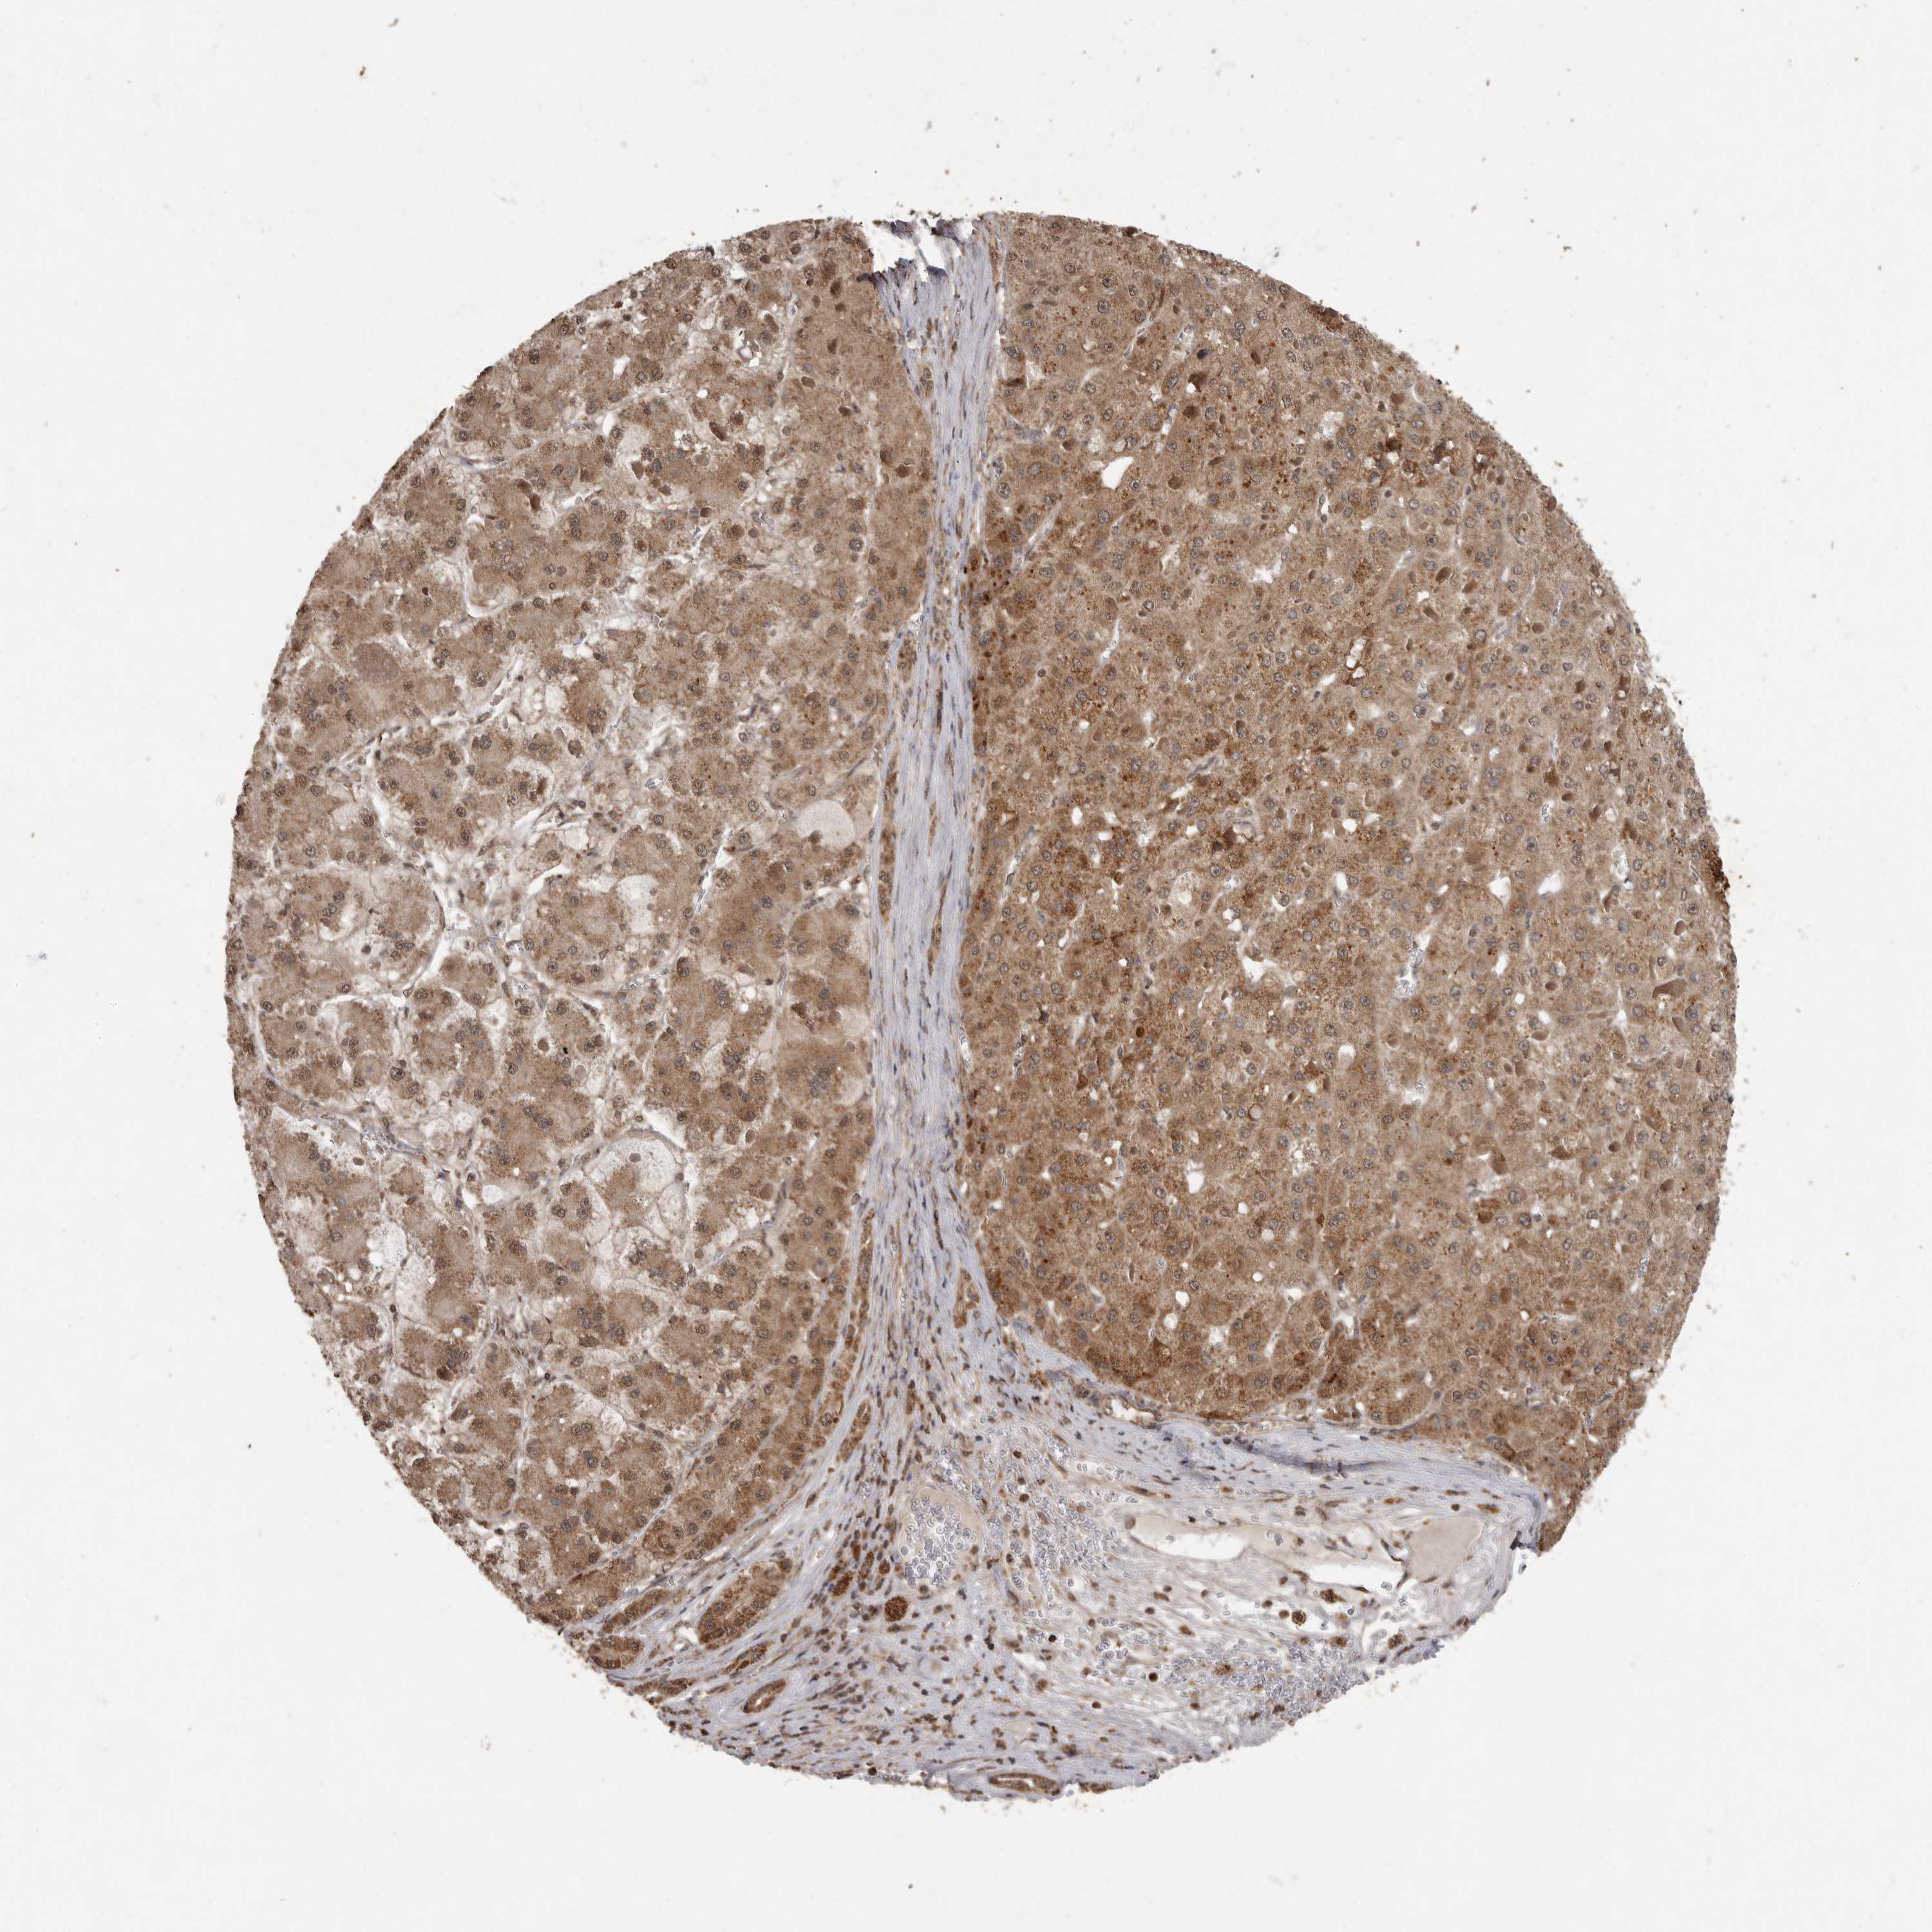

LIVER CANCER - Protein expressioni

A mouse-over function shows sample information and annotation data. Click on an image to view it in a full screen mode. Samples can be filtered based on level of antibody staining by selecting one or several of the following categories: high, medium, low and not detected. The assay and annotation is described here.

Note that samples used for immunohistochemistry by the Human Protein Atlas do not correspond to samples in the TCGA dataset.

Antibody stainingi

Antibody staining in the annotated cell types in the current human tissue is reported as not detected, low, medium, or high, based on conventional immunohistochemistry profiling in selected tissues. This score is based on the combination of the staining intensity and fraction of stained cells.

Each image is clickable and will lead to virtual microscopy that enables deeper exploration of all samples and also displays staining intensity scores, fraction scores and subcellular localization as well as patient and tissue information for each sample.

Antibody CAB025573

Staining

High

Medium

Low

Not detected

Intensity

Strong

Moderate

Weak

Negative

Quantity

>75%

75%-25%

<25%

None

Location

Nuclear

Cytoplasmic/membranous

Cytoplasmic/membranous,nuclear

Cholangiocarcinoma

Carcinoma, Hepatocellular, NOS